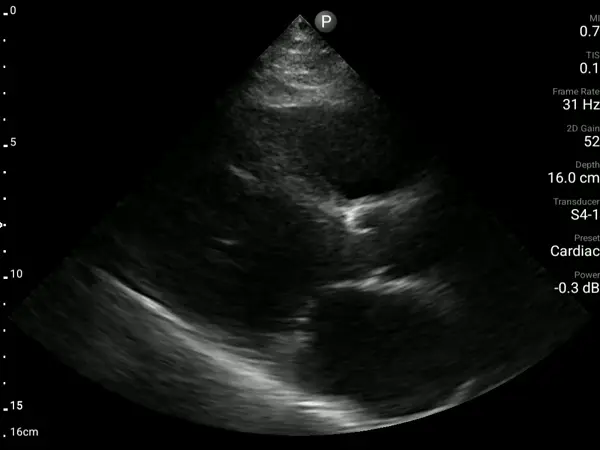

A 39-year-old woman with APLA syndrome returned to the ED three weeks after an emergency C-section with recurrent chest pain. Pulmonary embolism had been ruled out during a visit two days earlier, and an echocardiogram performed two months prior was normal (EF 60%).

A bedside AISAP exam revealed severe LV dysfunction, moderate RV dysfunction, severe MR, and mild pericardial effusion. These findings led to an urgent formal echocardiography and cardiology review, which established the diagnosis of postpartum cardiomyopathy.